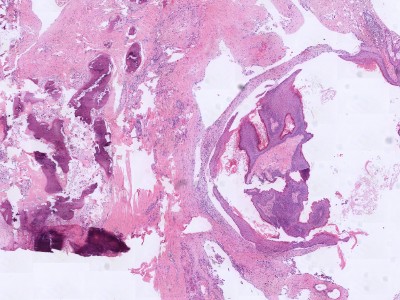

Histologie dermoid cyste Histologie dermoid cyste

ingescande coupe (zoom) ingescande coupe (zoom)